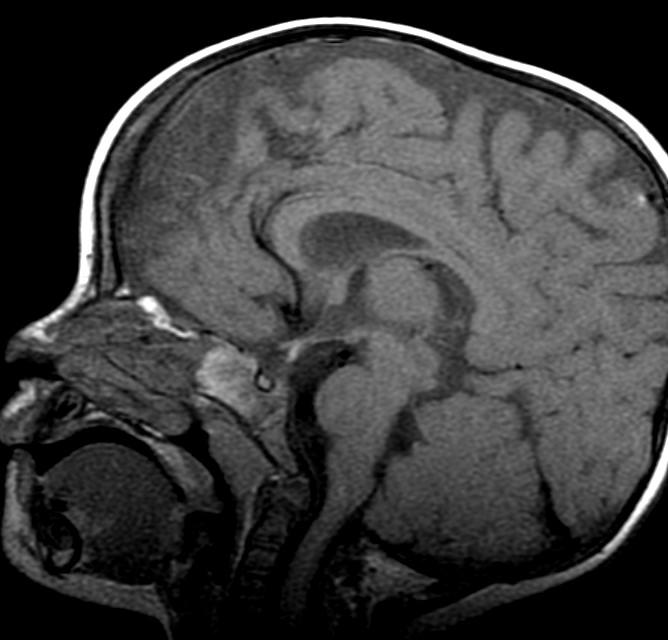

Blunted anterior Corpus, with subtle fusion at the level of the anterior commissure…?

Fusion (lack of cleavage) is just anterior /superior to the anterior commissure.

Ectopic posterior pituitary “bright spot.” Missing infundibular stalk.

Contrast or ultra thin T2 needed to confirm.